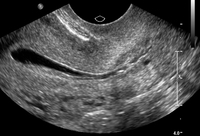

Normal saline infusion ultrasound

From the collection of Dr Jared C. Robins